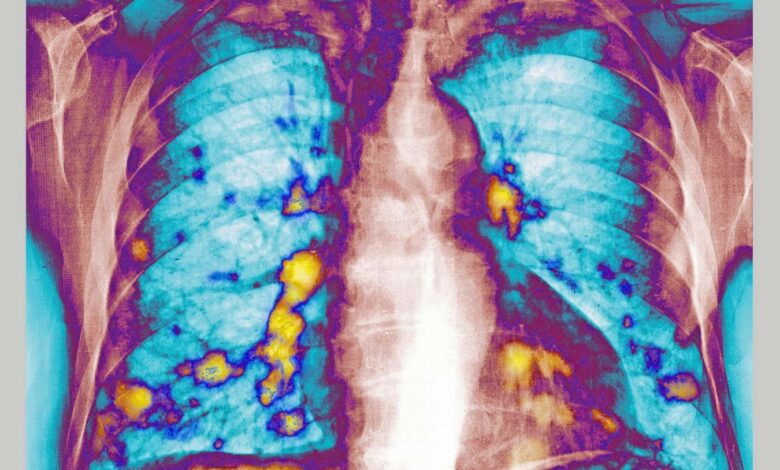

Cold-like RSV boosts lung immunity, slowing cancer spread

RSV lung – In mice, RSV and interferon responses temporarily make it harder for breast cancer cells to seed lung tumors—suggesting a potential anti-metastasis drug strategy.

Respiratory infections are increasingly on researchers’ radar because the lungs are a frequent landing site for cancer spread.. In studies involving mice. infecting animals with respiratory syncytial virus (RSV)—a common virus that causes cold-like symptoms and affects most people early in life—was linked to fewer breast cancer cells forming tumors in the lungs.